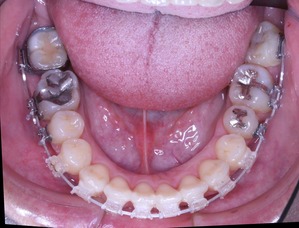

虫歯治療はきちんとされてますが、奥歯に全部銀歯の状態の歯があります。

当然、神経もない歯です。治療されたのはだいぶ前とのことでした。

しかしながら、いつ治療したか記憶にない銀歯があります。神経もとってしまってますし、中がどのような状態になっているか把握できません。治療中に歯がとれてしまい、結果的に抜歯となってしまう可能性もございます。

治療開始から3年経過した現在の状況です

上の歯列はどうでしょうか?